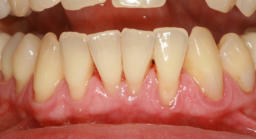

2. Transplantate für Zahnfleisch und Bindegewebe:

Durch Transplantate kann verlorenes Gewebe wieder aufgebaut werden. Damit wird eine dauerhafte Stabilität der Gewebe und damit auch des Knochens erzielt und eine gute Putzfähigkeit für Zähne oder Implantate erreicht. Beispiele: